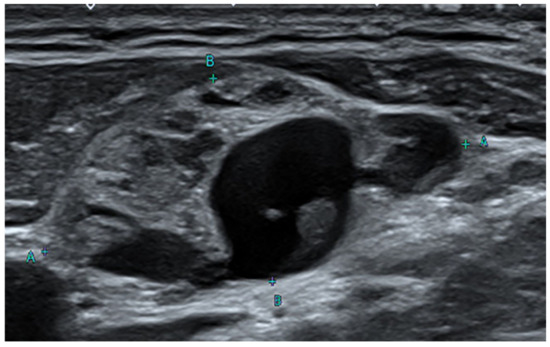

Gross findings of cervical lymph nodes (A) and right thyroid gland (B). (A) The cervical lymph node is enlarged 2.5 cm in maximum length. The cut surface of the lymph node shows a pale tan to brown solid appearance with cystic change. (B) The thyroid gland shows multiple variable-sized pale tan to brown solid and cystic nodules. In the areas of the superior thyroid artery and sternothyroid as well as enlarged cervical lymph nodes, benign thyroid tissues showed nodular proliferation with cystic changes. Some enlarged lymph nodes occupied almost the entire area (Figure 4A,B). Both thyroid lobes also had multiple follicular nodules covering almost all areas. Although follicular nuclei showed little irregularity in the nodular hyperplasia of the thyroid gland, atypical malignant cytologic features such as intranuclear grooves, pseudo-inclusions, and ground-glass appearances of nuclei were not observed (Figure 4C), except for an occult papillary microcarcinoma of a follicular variant (0.2 cm in diameter) in the remnant left thyroid (Figure 4E). The occult thyroid microcarcinoma was shown to be positive in the immunohistochemical staining for HBME-1, Galectin-3, and Cytokeratin 19. Among them, HBME-1 showed strong positivity (Figure 4F) compared to the surrounding benign thyroid tissue and nodular hyperplasia (Figure 4D).